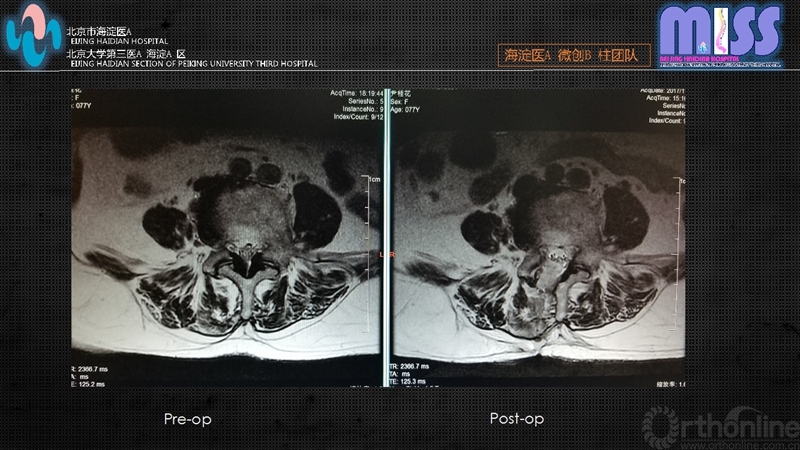

本组全部患者在12个月内得到完整随访,术后12个月时改良Macnab疗效评定:优24例,良6例,可4例,优良率88%。

通过对本组病例的随访观察,全内窥镜下单侧入路双侧减压技术,对老年中央型椎管狭窄及侧隐窝狭窄患者具有独特的优势,如:对患者全身情况要求低,术后恢复快,减少老年患者卧床并发症且该技术无需剥离椎旁肌,对腰椎后柱结构及肌肉韧带复合体破坏小。